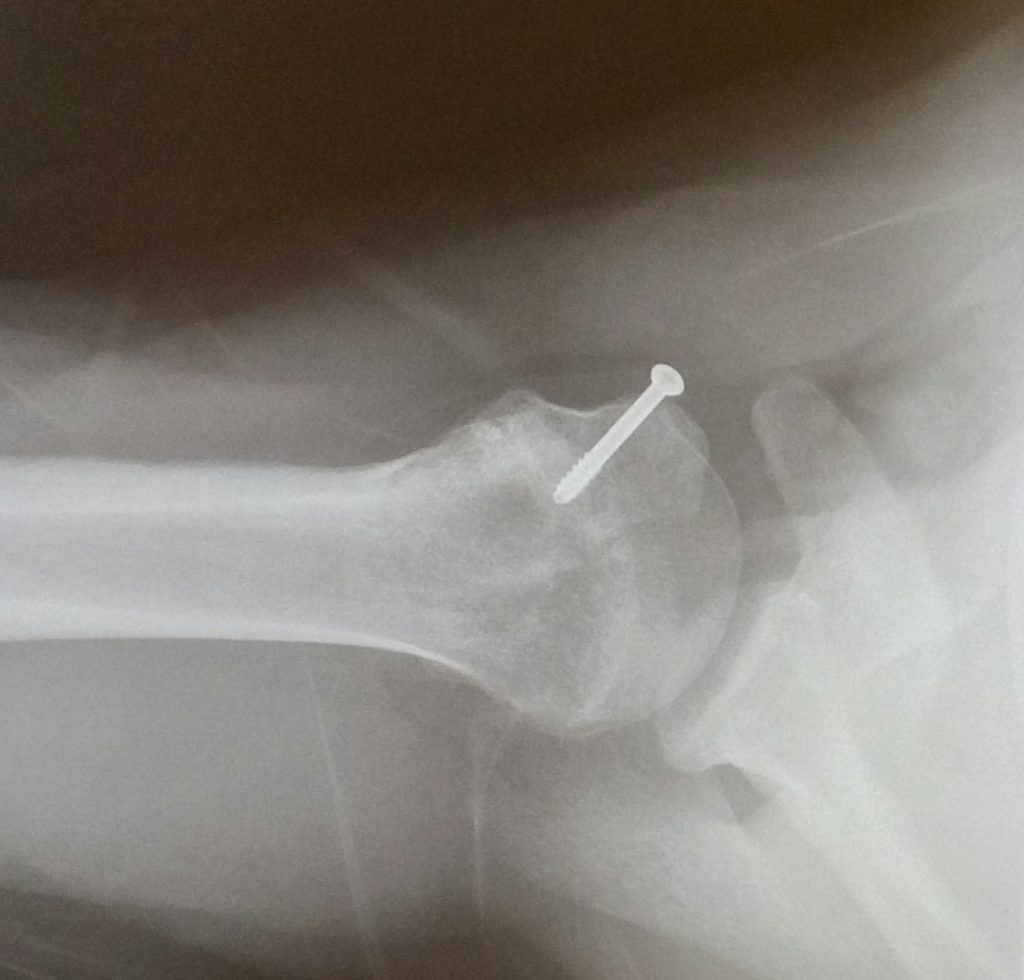

Fortunately I ended up being able to see Dr. Dines who had me in surgery within two weeks. Apparently not only did my bone grow/heal incorrectly, but I had a full labrum tear and scar tissue from the previous injuries. Dr. Dines performed a scope and a reconstruction on my shoulder. He repaired my labrum, cleaned out the scar tissue, relocated the bone and reattached my muscle. I have a screw and anchors holding it all together!